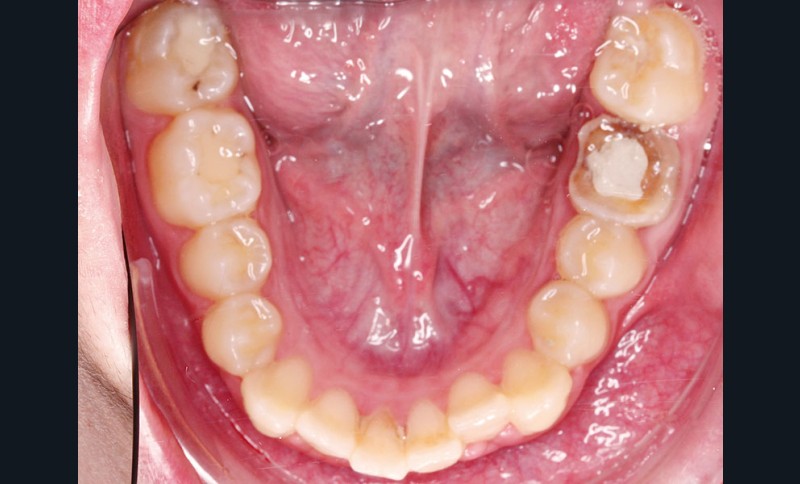

• Endo-buccal : Younesse présente un contrôle de plaque dentaire insuffisant, la persistance de 53 et 63, des soins en cours de réalisation sur 26 et 36, un encombrement maxillo-mandibulaire avec infravestibulotopie de 23 et une suspicion d’inclusion de 13 sur un schéma de Classe II subdivision droite (fig. 3 à 7).